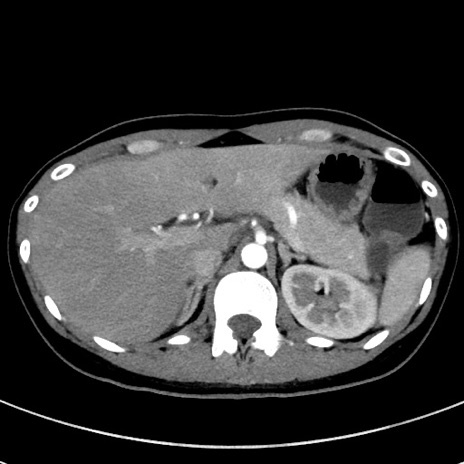

冠状断像

【症例】20歳代女性

【主訴】嘔吐、下腹部痛

【現病歴】昨日夕食後に嘔吐し下腹部痛が出現。本日になっても嘔吐持続し改善しないため来院。

【身体所見】意識清明、BT 37.2℃、BP 108/67mmHg、腹部:平坦、やや硬、下腹部正中から右にかけて圧痛あり、反跳痛軽度あり、tapping pain(+)。

【データ】WBC 13600、CRP 14.94